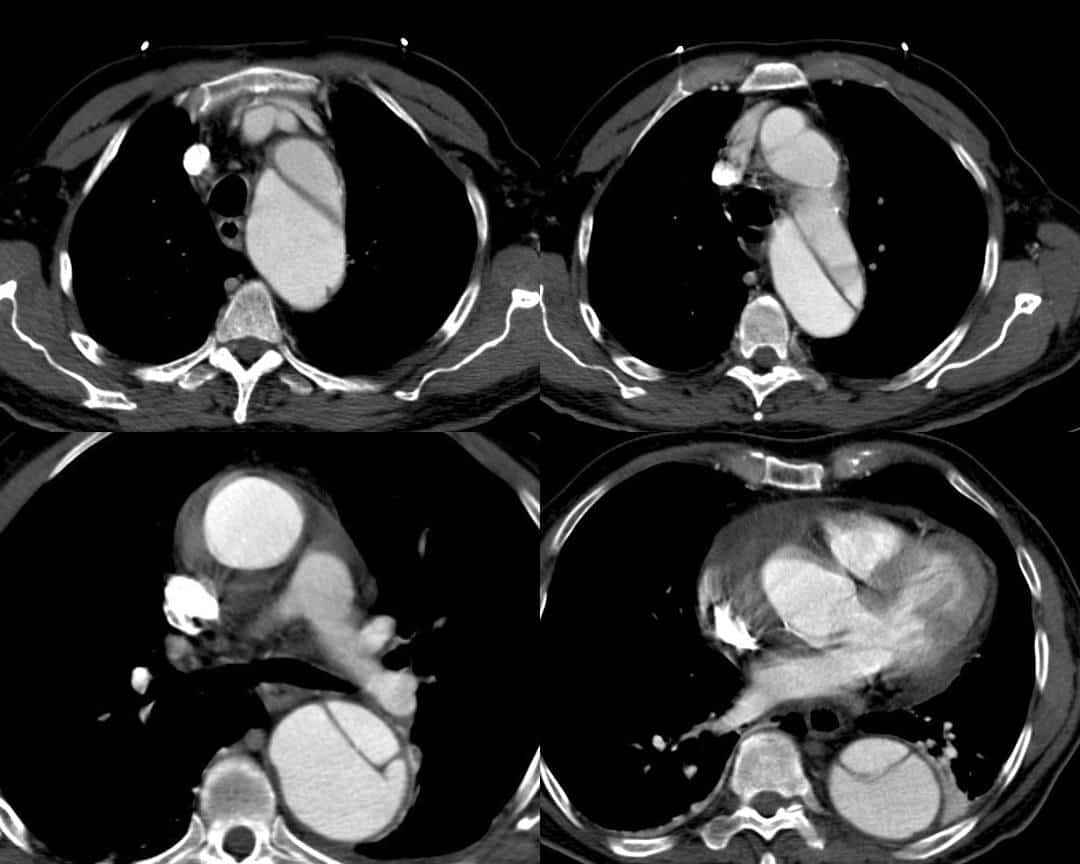

Bóc tách ĐM chủ ngực

» Thông tin: Nam giới – 72 tuổi.

» Lâm sàng: Đau ngực.